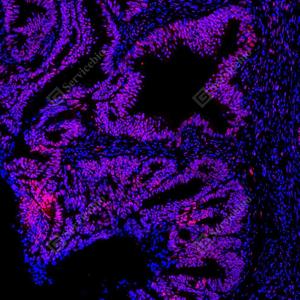

| IF检测phospho-STAT1 (S727)蛋白(货号 GB150117)(红色). 样品: 人结肠癌, 4%多聚甲醛 (货号G1101) 固定12-24小时. 抗原修复: Tris-EDTA抗原修复液(pH 9.0) (G1203), 100℃, 25分钟. 封闭: 3% BSA(货号GC305010)的PBS溶液, 室温孵育30分钟. —抗: 1: 4000稀释, 4℃ 孵育过夜. 二抗: Cy3标记山羊抗兔IgG (H+L) (货号GB21303), 1: 300稀释, 室温孵育1小时. |